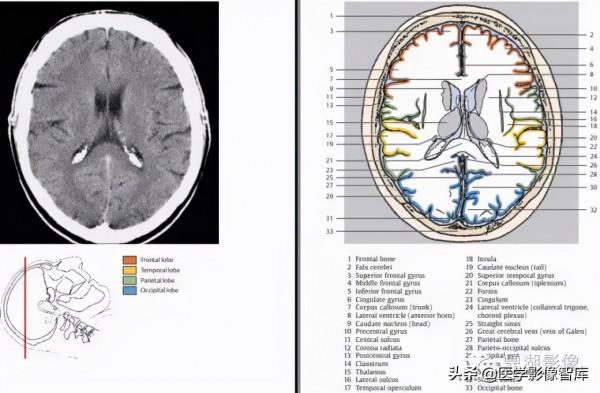

1.額骨 2.額上回 3.大腦鐮 4.額中回 5.扣帶回 6.冠狀縫 7.胼胝體周圍動脈 8.中央前回 9.放射冠 10.中央溝11.胼胝體 12.中央後回13.側腦室(脈絡膜叢) 14.中央後溝 15.頂骨 16.緣上回 17. 楔前葉 18.角回 19.頂枕溝 20.枕回 21.楔葉 22.枕骨 23.上矢狀竇

1.額骨 2.大腦鐮 3.額上回 4.額中回 5.額下回 6.扣帶回 7.胼胝體幹 8.側腦室前角 9.尾狀核頭10.中央前回 11.中央溝 12.放射冠 13.中央後回 14.屏狀核 15.丘腦 16.外側裂 17.顳葉島蓋 18.腦島 19.尾狀核尾 20.顳上回 21.胼胝體壓部 22.穹窿 23.扣帶回峽 24. 側腦室脈絡叢 25.直竇 26.大腦大靜脈27.頂骨 28.頂枕溝 29.枕回 30.楔葉 31.上矢狀竇 32.紋狀皮層(視覺初級皮層)33.枕骨